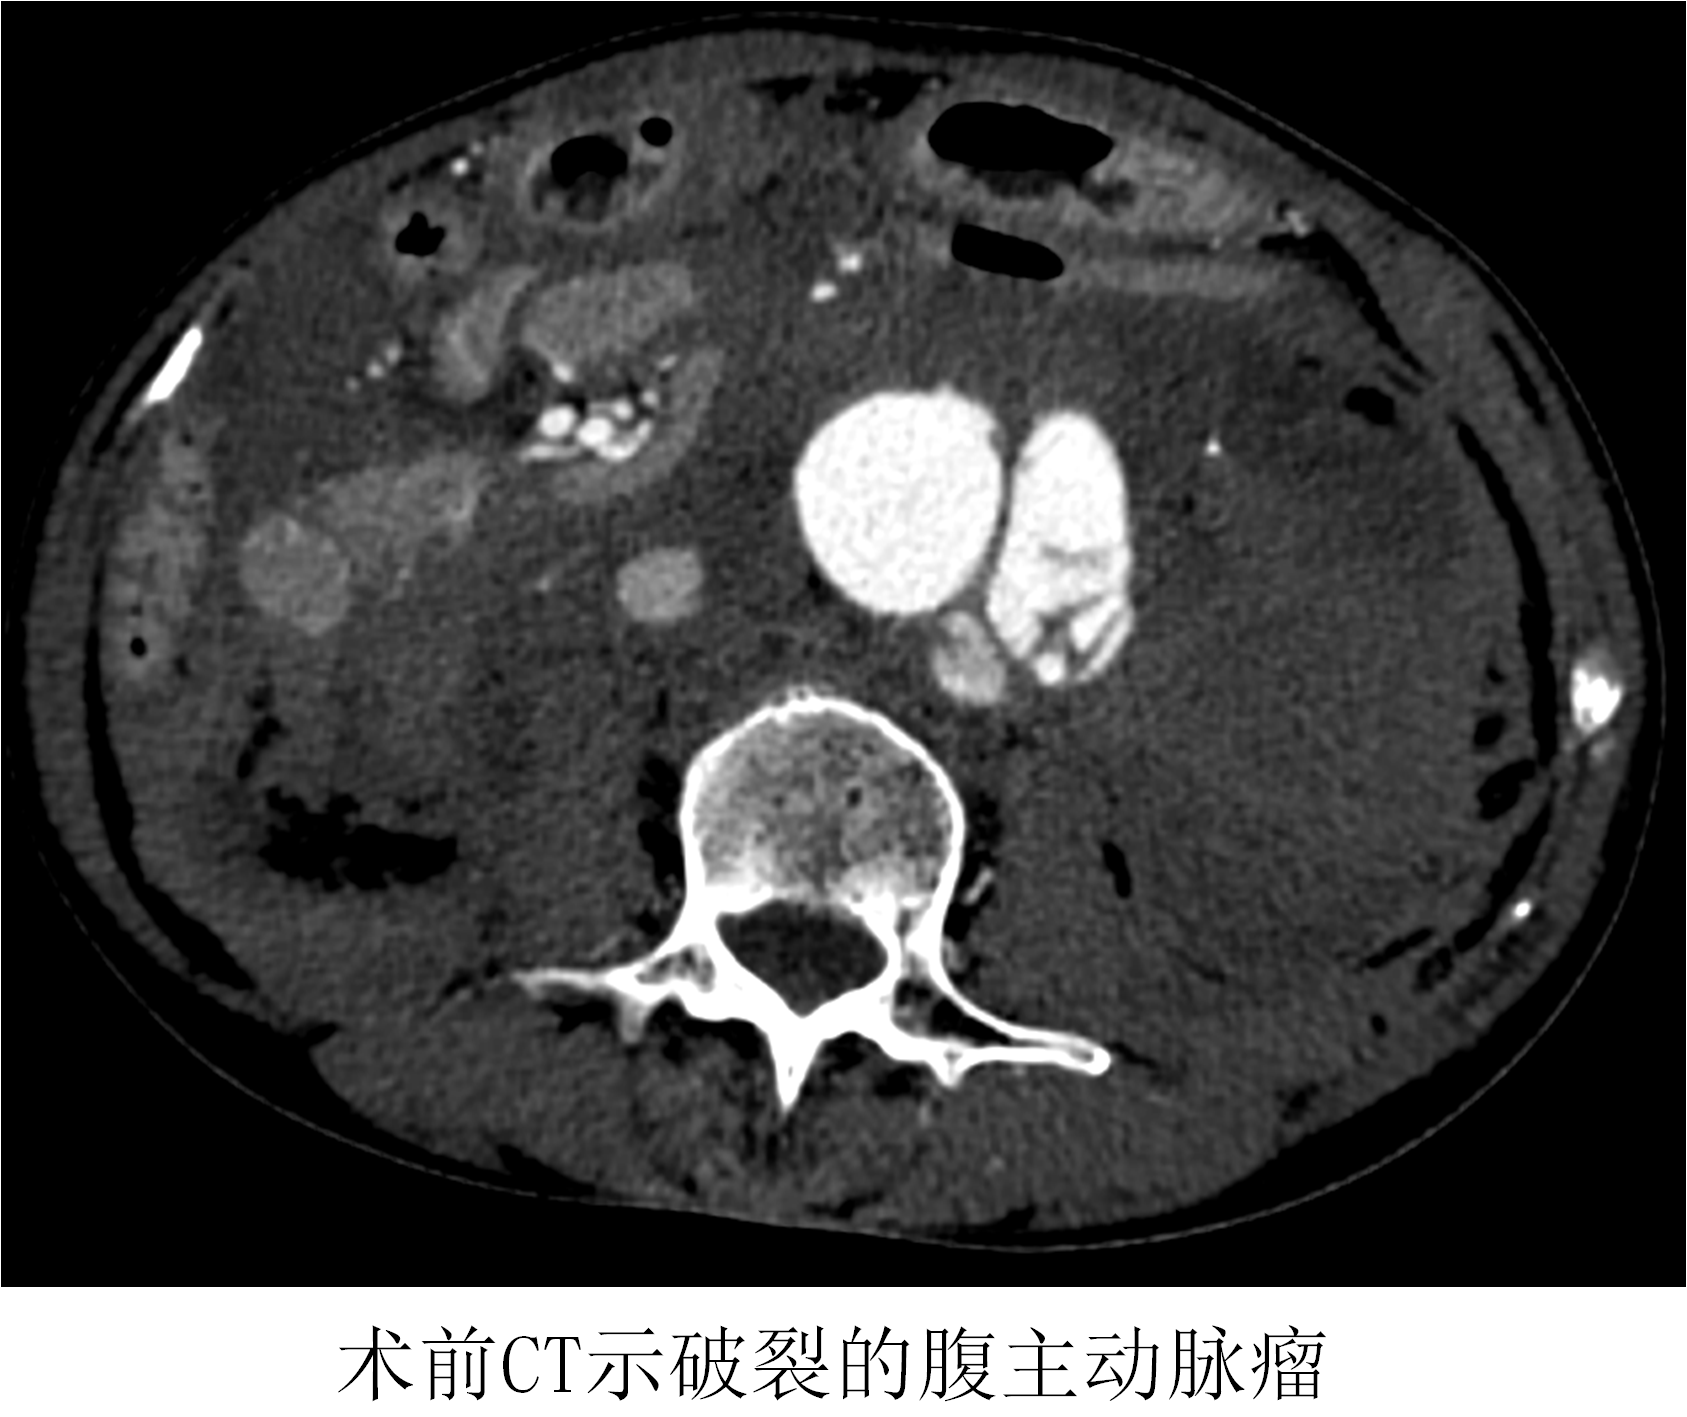

薛冠華在得知患者情況后,立刻從家中趕往醫(yī)院,開始了這場與死神的賽跑。患者在急診抗休克治療的同時,半小時內(nèi)完成所有檢查,隨即被送入復(fù)合手術(shù)室。此時患者的血壓繼續(xù)下降,最低時只有60/30mmHg。

時間就是生命!在來不及全麻的情況下,薛冠華當(dāng)機立斷,局麻手術(shù)。手術(shù)由薛冠華主刀、倪其泓和王預(yù)立醫(yī)師共同協(xié)助,在麻醉醫(yī)師黃丹、手術(shù)室護士夏悅和放射科技師馬鋆的配合下緊張進行。薛冠華通過精準(zhǔn)定位,在避免影響內(nèi)臟血管的同時,采用腔內(nèi)技術(shù)在短短30分鐘內(nèi)就將腹主動脈瘤的破口通過覆膜支架封堵,有效阻止了進一步出血。患者的血壓開始回升,情況逐漸平穩(wěn),手術(shù)順利完成。患者轉(zhuǎn)入重癥監(jiān)護室后意識慢慢恢復(fù),術(shù)后10天復(fù)查CT顯示破裂的腹主動脈瘤隔絕良好,已于近期康復(fù)出院。